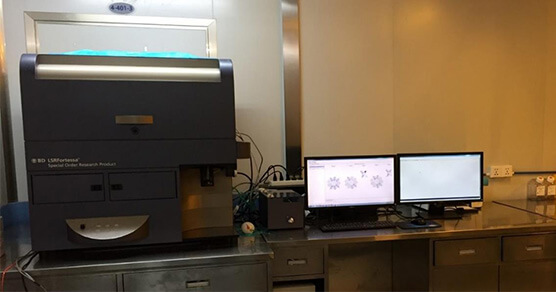

相关实验室

相关实验室